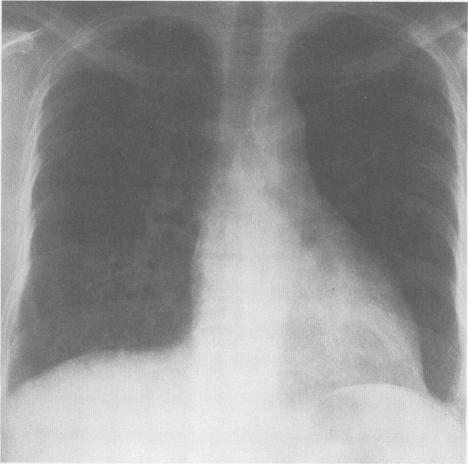

Sarcoidosis is a multisystem granulomatous disorder of unknown cause that presents most frequently in young adults with bilateral hilar adenopathy, pulmonary infiltrates, and skin or eye lesions. The multisystem clinical manifestations of this disease are a diagnostic challenge to all physicians. Although the clinical and pathologic characteristics of sarcoidosis are well described, the decision to treat and the optimal therapy are less well defined. This review focuses on the natural history, clinical manifestations, controversies in therapy, including steroid-sparing agents, and current concepts of how the disease's activity can be monitored.

结节病是一种病因不明的多系统肉芽肿性疾病,最常见于年轻成年人,表现为双侧肺门淋巴结肿大、肺部浸润以及皮肤或眼部病变。该疾病的多系统临床表现对所有医生来说都是一个诊断挑战。尽管结节病的临床和病理特征已有详尽描述,但关于治疗决策和最佳治疗方法的界定却不够明确。本综述聚焦于结节病的自然病程、临床表现、治疗方面的争议(包括糖皮质激素节省剂)以及目前关于如何监测该疾病活动的理念。